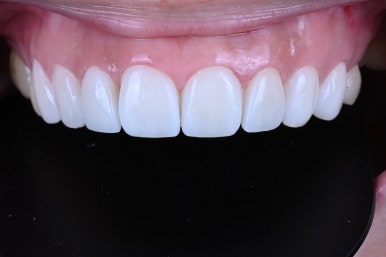

그리하여 완성된 레브네이트 엑스퍼트..

화사한 색감이 생겼습니다.

그리고 도자기처럼 반딱거리는 인공적인 느낌이 아니라, 표면에 세라믹 가공을 첨가하여 약간의 텍스처를 부여한 덕에 자연스러움까지 추가되었습니다.

뭔가 밝아지긴 했는데... 하얘진건 맞는데 자연스럽다는 것..

이게 뭐라 설명하기 어려운 작품의 세계라고 해야할 것 같아요.

어디에서 보아도 원래 치아의 어두웠던 색상은 보이지 않고,

치아가 너~무 말 이빨처럼 커보이지도 않고, 자연스러운 생김새를 갖고 있습니다.

아래 치아와 비교해보시면 더욱 더 뚜렷한 색상차이를 확인하실 수 있죠.

입안에 위치하고, 눈코입과 함께 보면 요 색상이 꽤나 자연스러움을 아실 수 있으실겁니다.

Before & After

전과 후를 비교해보시면, 얼마나 자연스럽게 예뻐졌는지 확인하실 수 있으실거에요.

분명 색상도 개선되고 형태도 개선되었는데, 한편으로 자연스러운 매력.

레브네이트 엑스퍼트의 활약 덕분입니다 ^^

그리고 확실히 레브네이트 접착 후에 웃음이 더 자연스러워지고, 입술 모양도 더 예뻐졌어요!

앞니만 봤을 때도, 확실히 다른 느낌인 것을 확인하실 수 있어요.

치아의 가로-세로 비율이 좋아졌고, 좌우 대칭이 상당히 좋아졌습니다.

얼굴형과 어울리는 치아의 모양을 갖게되셔서, 참 결과가 좋았던 기억..^^